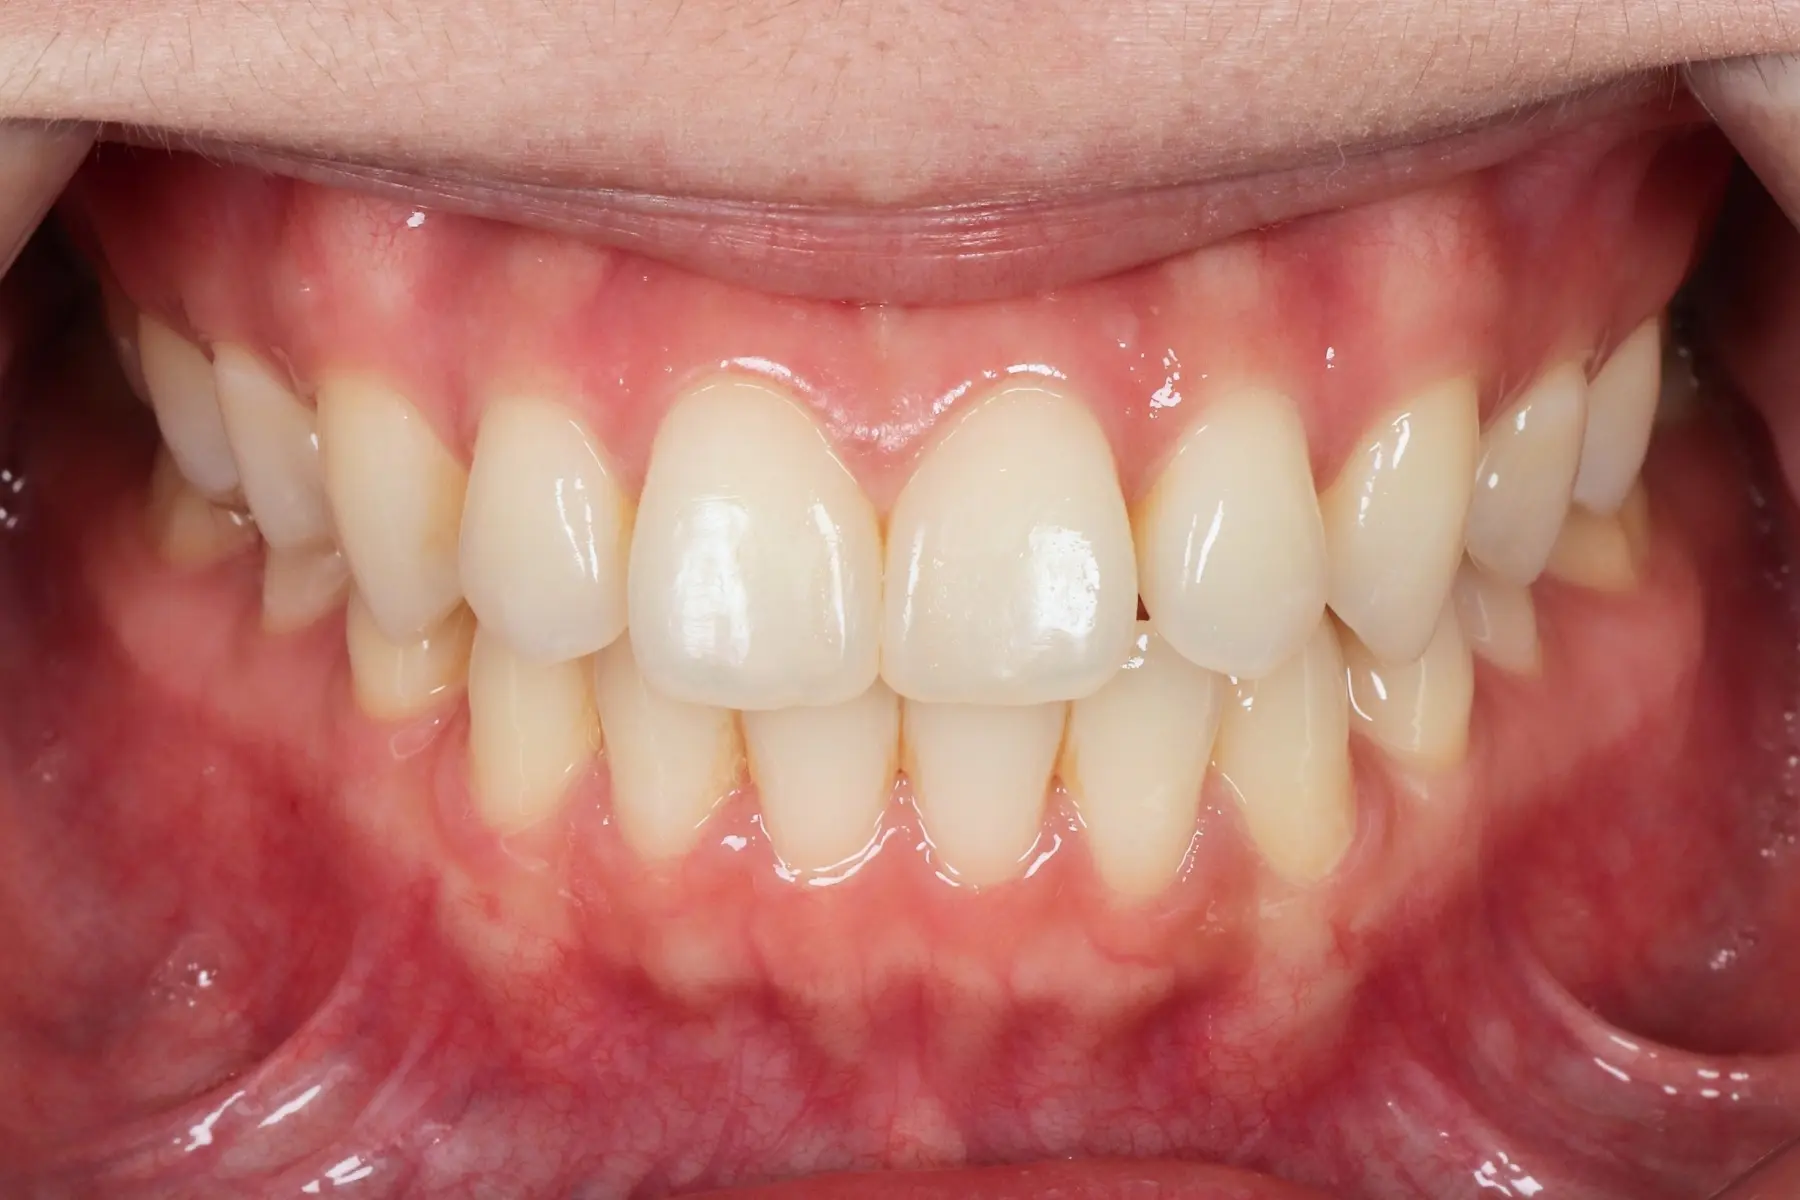

Dentist 陳昕 全口照護醫師 看診項目 前牙美學仿生樹脂補牙/全科牙醫 學經歷 臺北醫學大學牙醫系學士 前天主教新店耕莘醫院醫師 前臺北榮民總醫院醫師 亞洲齒列再生研究學會Advance植牙補綴專科訓練 微光私塾牙周雷射微創治療技術訓練 臺灣牙醫顯微美學治療學會會員醫師 中華審美牙醫學會會員醫師 CASE 案例分享 滲透型樹脂修復 主治醫師 陳昕 治療時間 單次療程 主訴 想處理前牙白白的色斑 前牙美學/仿生美學樹脂 主治醫師 陳昕 治療時間 單次療程 主訴 牙齒整齊,但門牙中間縫隙明顯,影響笑容美觀 前牙美學/陶瓷貼片 主治醫師 陳昕 治療時間 約1個月 主訴 兩顆門牙缺角,想要重建外觀 前牙美學/滲透型樹脂修復 主治醫師 陳昕 治療時間 單次療程 主訴 門牙有長期存在的白斑與表面不平整,影響外觀與自信 前牙美學/仿生美學樹脂 主治醫師 陳昕 治療時間 約兩週 主訴 矯正後的黑三角縫問題 前牙美學/仿生美學樹脂 主治醫師 陳昕 治療時間 約三週 主訴 因牙周病產生的黑三角縫 前牙美學/牙冠增長術、仿生全瓷牙冠 主治醫師 陳昕 治療時間 約6個月 主訴 牙齒排列不整、假牙外觀不自然 前牙美學/仿生美學樹脂 主治醫師 陳昕 治療時間 約兩週 主訴 露齒笑時黑三角縫明顯,覺得不好看 前牙美學/仿生美學樹脂+噴砂美白 主治醫師 陳昕 治療時間 約兩週 主訴 露齒笑時有不好看的黑三角縫,容易有茶垢沉澱,讓縫隙更明顯 牙齒美白/噴砂美白+冷光美白 主治醫師 陳昕 治療時間 單次療程 主訴 前牙泛黃且染色明顯,影響外觀與自信 牙齒美白/噴砂美白 主治醫師 陳昕 治療時間 單次療程 主訴 牙齒表面有喝咖啡、抽菸造成的外部染色,影響外觀與自信 點此載入更多 Column 精選文章 FEATURED 精選案例 【牙科修復案例】陶瓷貼片可以做一顆嗎?單顆門牙缺角修復,陶瓷貼片重建自然笑容 2026-01-16 從「假笑」到「自然笑容」的轉變——認識「牙冠增長術」與「仿生全瓷冠」 2025-10-14 Video 精選影音